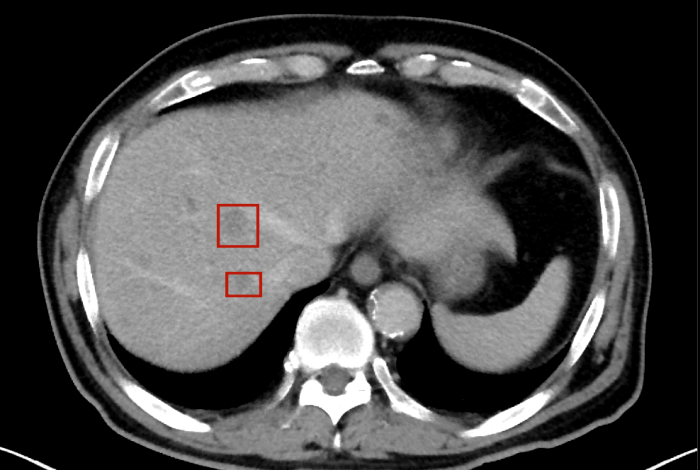

術(shù)后,萬秀萍為黃先生做進(jìn)一步的檢查,腹部磁共振(MRI)檢查顯示:肝臟區(qū)域出現(xiàn)了轉(zhuǎn)移病灶的陰影。

轉(zhuǎn)移病灶的陰影

目前,黃先生的腫瘤活動已得到有效抑制,肝臟轉(zhuǎn)移灶未見爆發(fā)性進(jìn)展,病情整體保持穩(wěn)定。